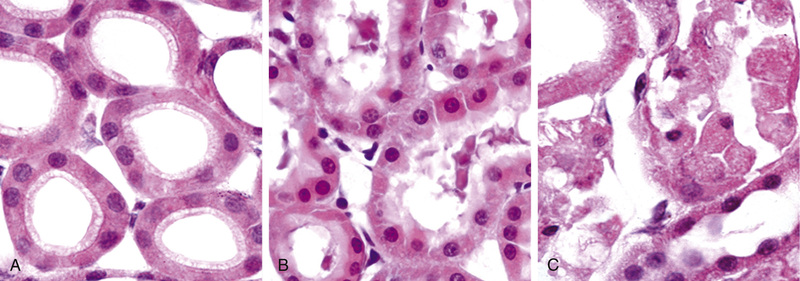

Proteins. Morphologically visible protein accumulations are less common than lipid accumulations; they may occur when excesses are presented to the cells or if the cells synthesize excessive amounts. In the kidney, for example, trace amounts of albumin filtered through the glomerulus are normally reabsorbed by pinocytosis in the proximal convoluted tubules. However, in disorders with heavy protein leakage across the glomerular filter (e.g., nephrotic syndrome), much more of the protein is reabsorbed, and vesicles containing this protein accumulate, giving the histologic appearance of pink, hyaline cytoplasmic droplets. The process is reversible: if the proteinuria abates, the protein droplets are metabolized and disappear. Another example is the marked accumulation of newly synthesized immunoglobulins that may occur in the RER of some plasma cells, forming rounded, eosinophilic Russell bodies. Other examples of protein aggregation are discussed elsewhere in this book (e.g., “alcoholic hyaline” in the liver in Chapter 16; neurofibrillary tangles in neurons in Chapter 23).